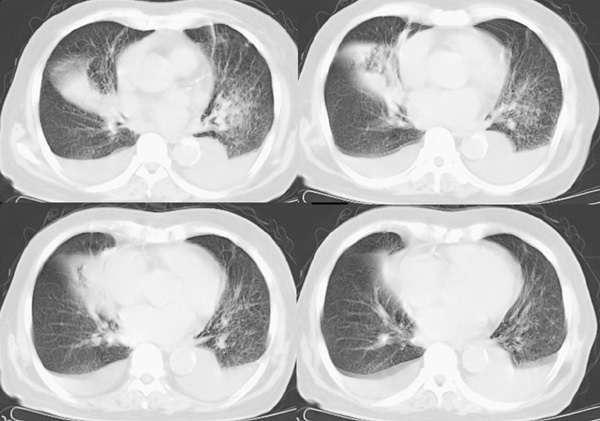

以下是引用panyishengct在2008-5-19 21:48:00的发言:[br]左侧胸壁脂肪瘤;肺部还是考虑肺水肿,胸腔积液。 [br] [br]左肺门见一团状影,纵隔见淋巴结,建议治疗后复查,以排外中央型肺癌

以下是引用形影不离在2008-5-19 21:13:00的发言:[br]左侧胸壁脂肪瘤;肺部还是考虑心衰并肺水肿,胸腔积液。